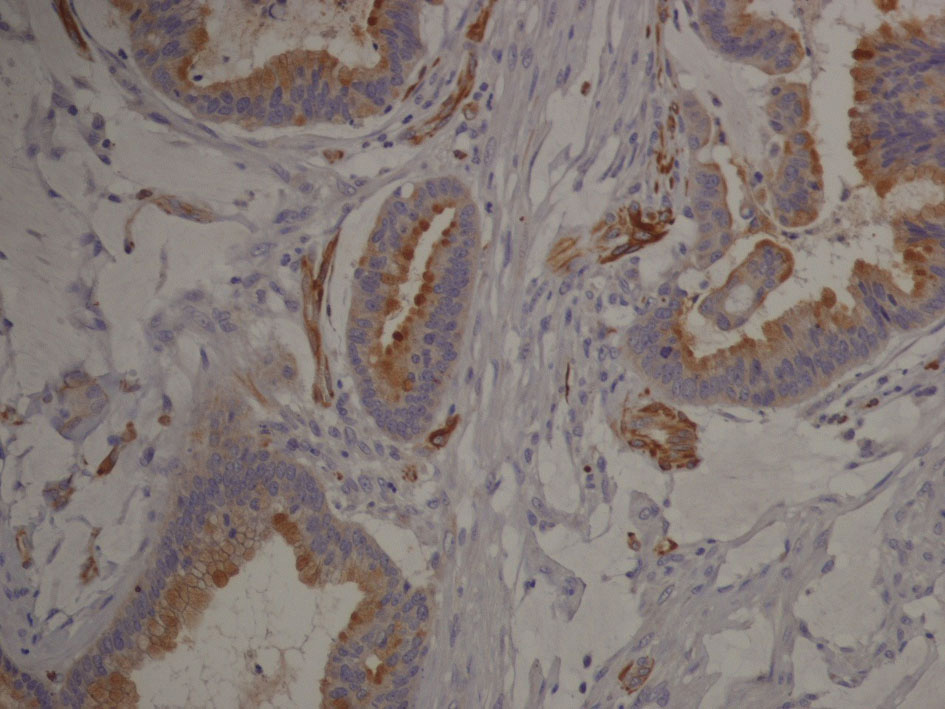

Immunophenotype was: cytocheratine 20+, CDX2a+, cytocheratine 7-, WT1-, negative estrogen and progesteron receptors; stromal and vascular invasion was observed (Fig. 6, 7).

![]() Click for large image | Figure 7. Immunophenotype image (hight magnification): tumor cells expressing cytocheratin 20 are organized in glandular structures and show vascular and stromal invasion. |